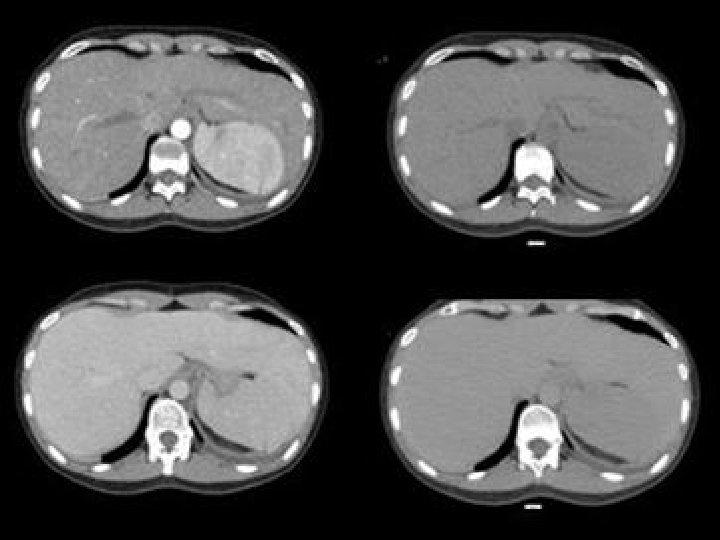

Protocolo de estudio • Sin contraste • Fase precoz • Fase v-p • Tardía

Protocolo de estudio • Sin contraste • Fase precoz • Fase v-p • Tardía 5 minutos

Protocolo de estudio • Sin contraste • Fase precoz • Fase v-p • Tardía 5 minutos SI O SI PARA VER BAZO